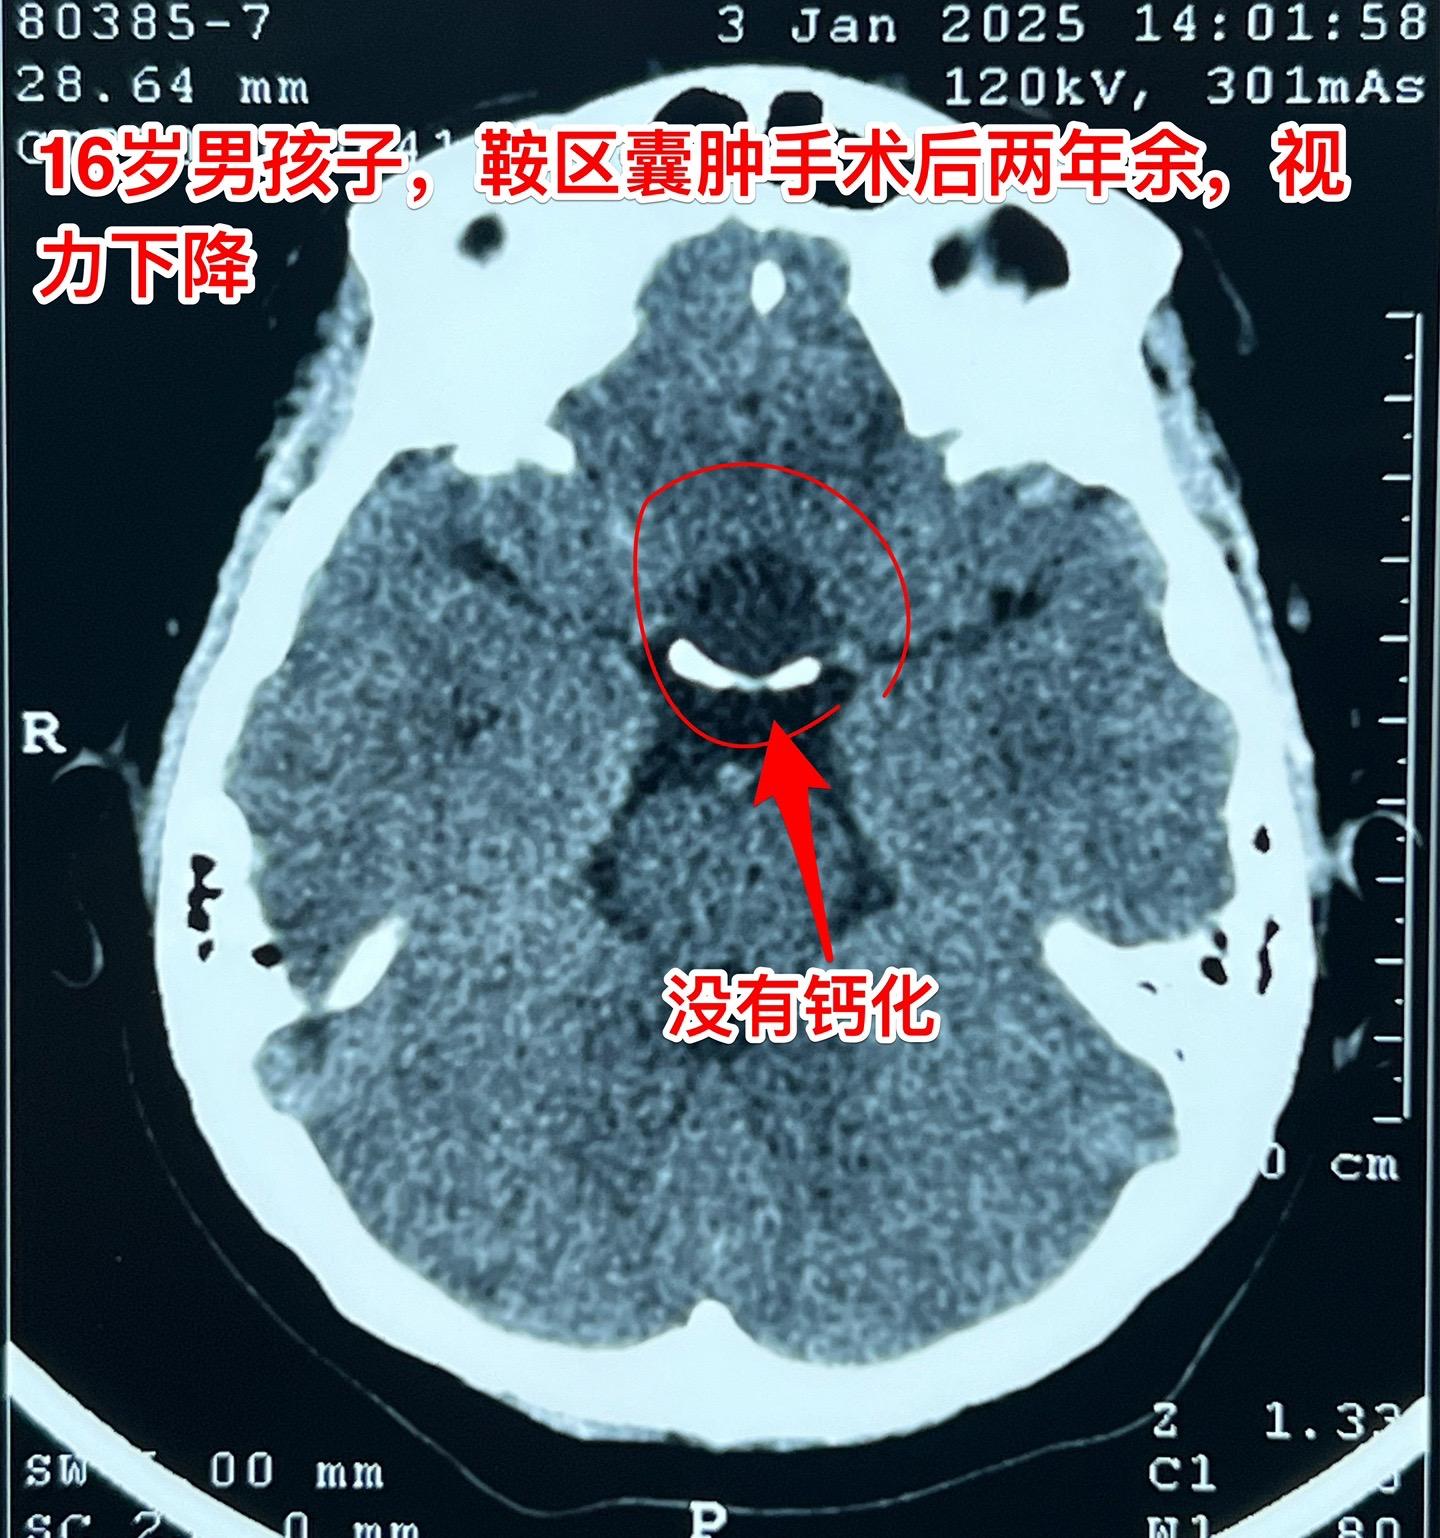

鞍区囊肿不能说是小问题(确诊拉克氏囊肿)16岁的男孩子2年前就因多饮多尿症状到医院检查发现鞍区囊肿,怀疑是拉克氏囊肿。这个病不是真性肿瘤,但是也不是小问题,也会导致尿崩症、生长发育迟缓、视力下降等问题。 他们一家选择了一个著名的医院去作手术,采用经鼻手术方式。遗憾的是手术中取得的标本最终未得出确切的病理诊断。手术后小孩子还出现了脑脊液鼻漏、颅内感染,受老罪了。 随后两年多时间内多次复查磁共振显示囊肿复发了,而且出现视力下降。然而小孩子对于第一次手术的痛苦印象太深了,故而拒绝作第